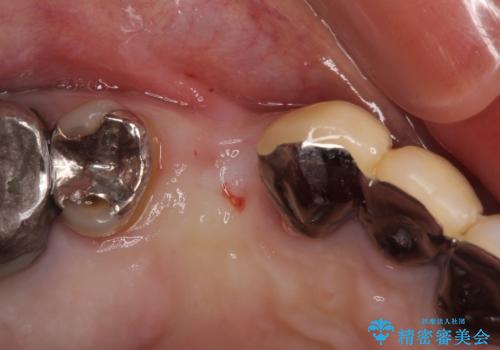

- 他院で抜歯が必要と診断され、インプラント治療を希望して来院された患者様です。

より審美的で、より機能的に優れた治療をご希望とのことであったので、ジルコニアカスタムアバットメントを用いたインプラント治療を行うこととしました。